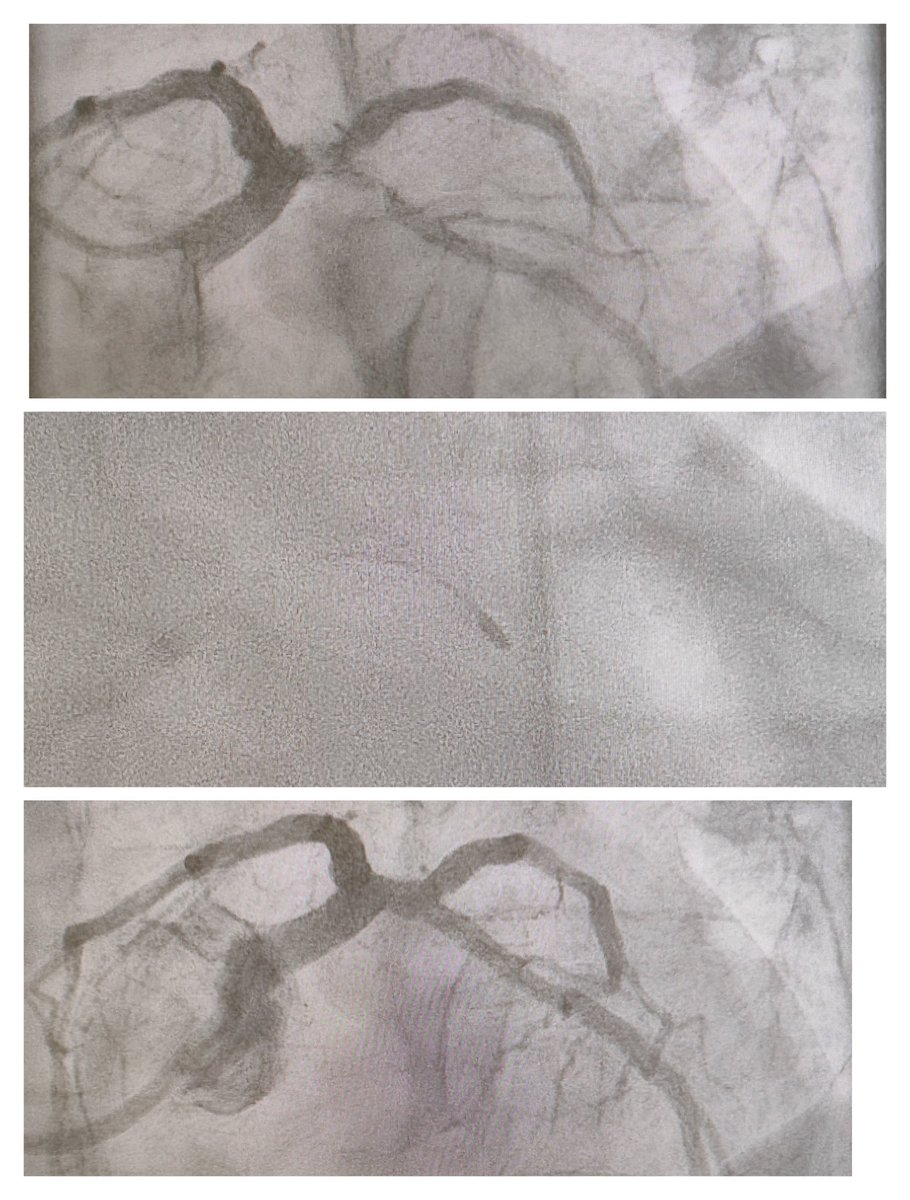

w_jyg's tweet image. First #RotaPro use in our centre.

#ESRD Diffuse heavily #calcified LAD

#IVUS near 360

1.5 #burr #170krpm x 5 runs

NC 3.0, #DES x2 , NC 4.0